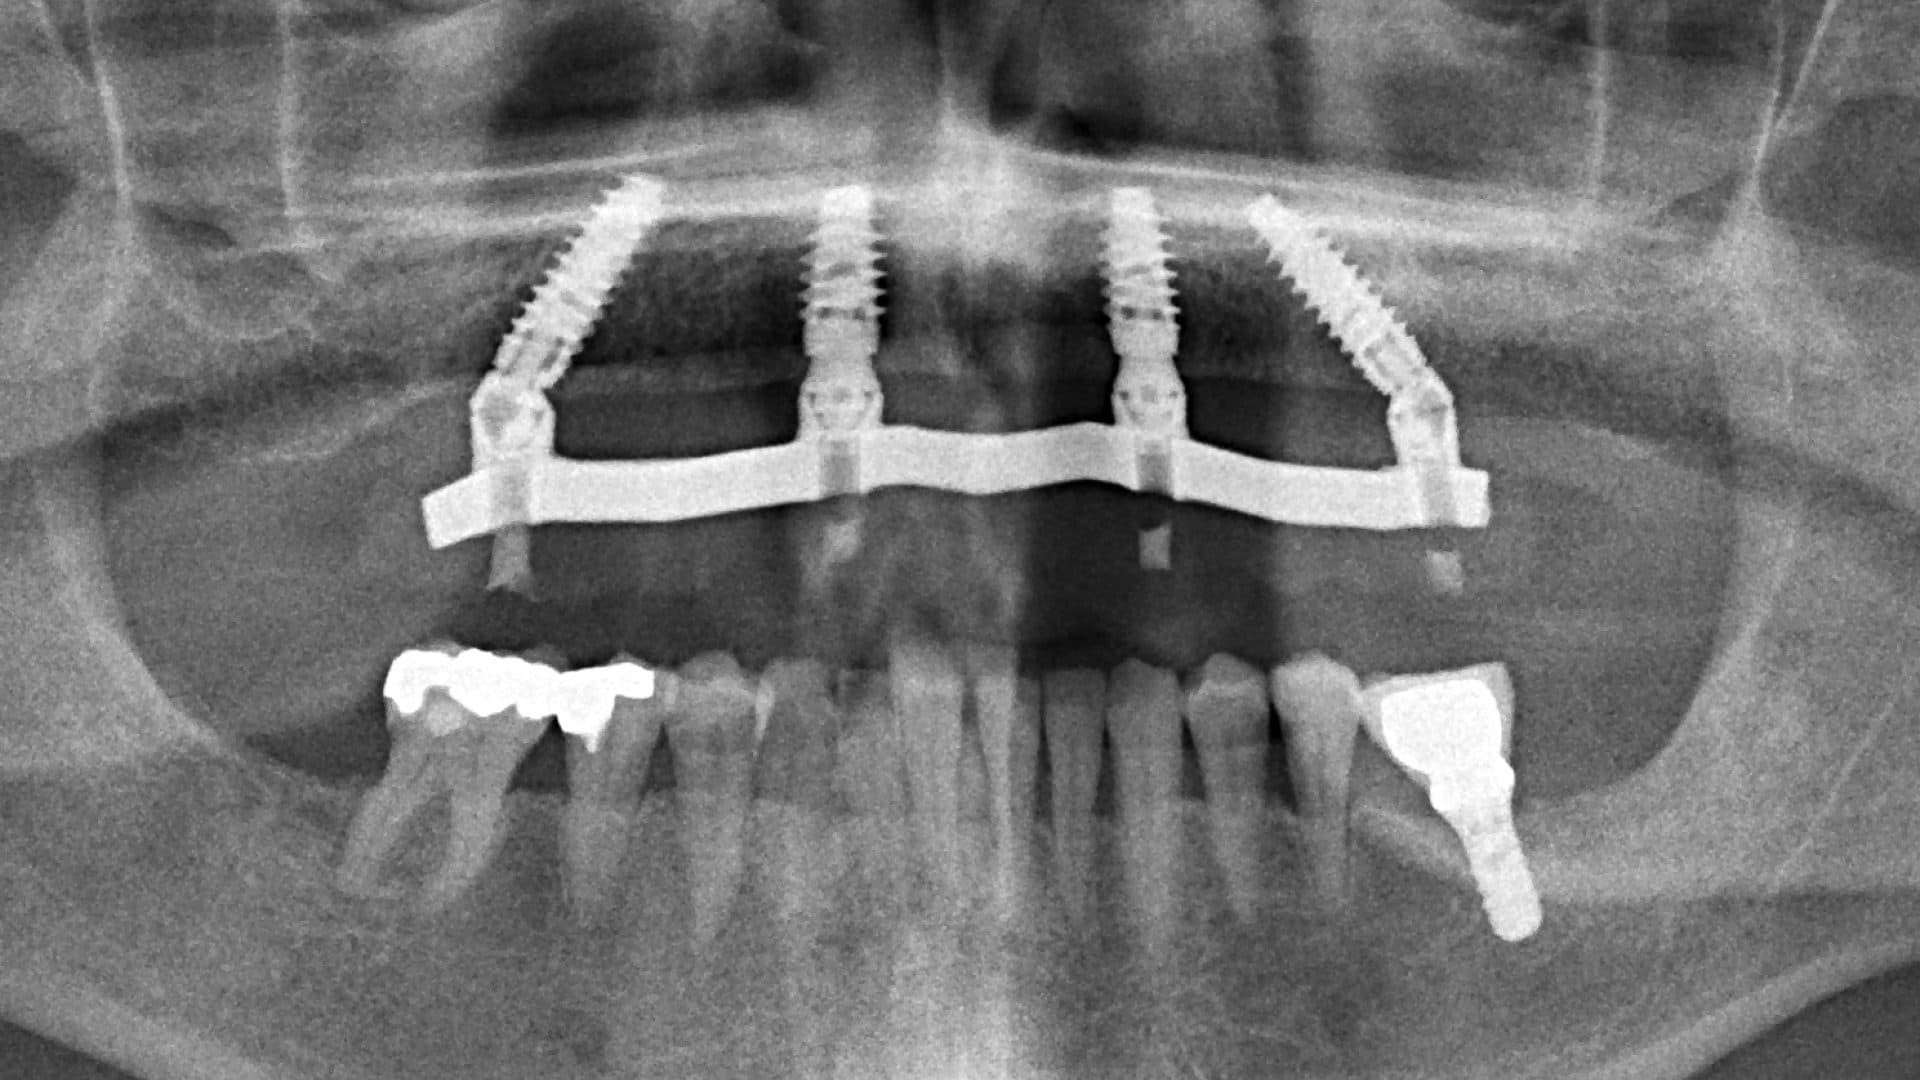

Here is a graphical overview of the ideal situation compared to poor standards with All-on-4 Plus® dental implants.

Ideal Situation

Poor Standards

As the surgery involves the jawbone, which is often already deficient, this treatment is difficult to undo and almost impossible to redo. This is surgery that also involves the mouth, which you use to talk, eat, taste, kiss, and smile, and when done incorrectly the treatment, being irreversible in its nature, could potentially commit a patient to a lifetime of new problems. Thus, as trusted clinicians we must always aim to get it right in the first place, but how can the patient know whom to trust?